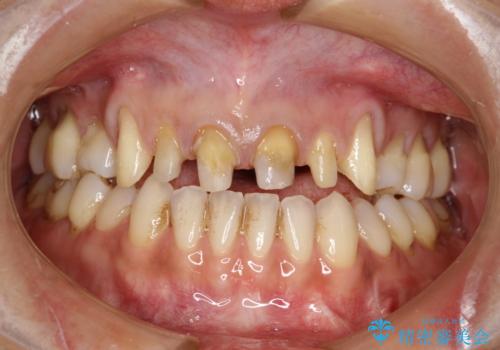

- 昔装着した前歯のかぶせ物を新しくしたいとのことで来院されました。

ご自身の歯とかぶせ物の境目が露出しておりました。

また犬歯の形も気になるとのことでした。

前歯の合計6本をオールセラミッククラウンにする計画としました。

以前に装着されていたものは全て連結されており、清掃性があまり良くありませんでした。